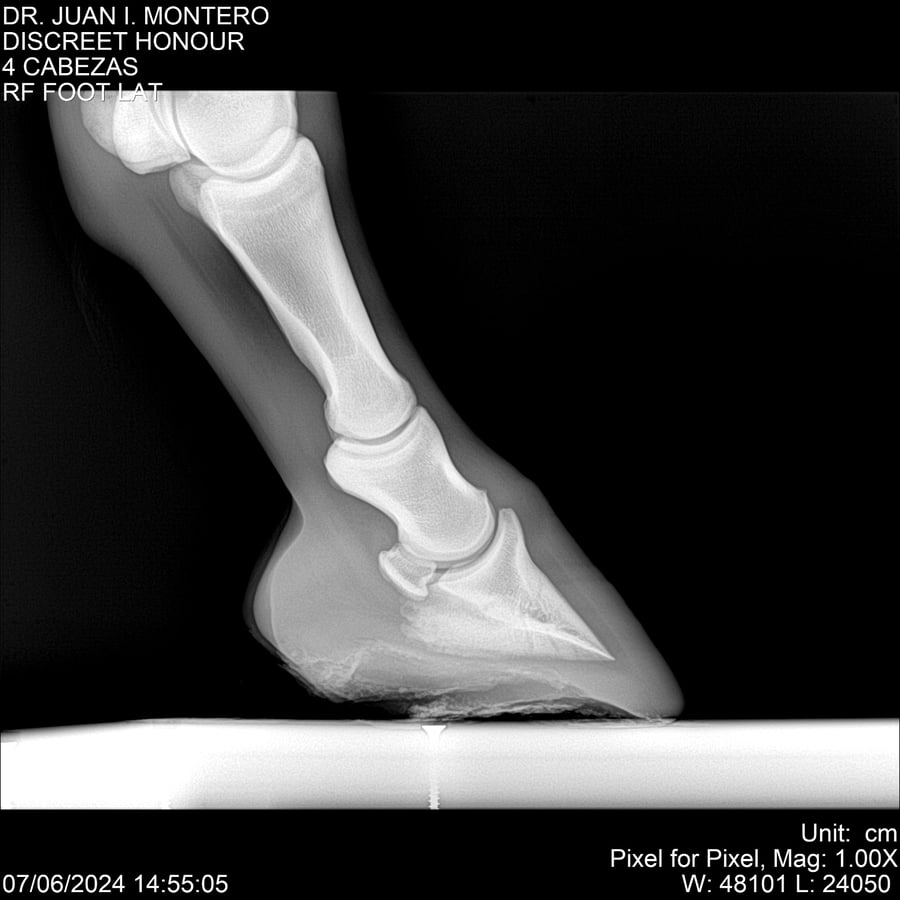

LOTE 6, DISCREET HONOUR 🔥 🔥 🔥 Lote Anterior Volver al remate Lote Siguiente Ficha Contacto Montevideo - Ficha del Lote Identificador: #281093 Categoría: Yeguarizos Montevideo - 82 Visualizaciones ClicData Contacto Empresa: Abelenda N. R., Walter Hugo Nombre*: Teléfono* : E-mail* : Mensaje Enviar Registrese gratis Este contenido Exclusivo está disponible sólo para usuarios registrados Ingresar